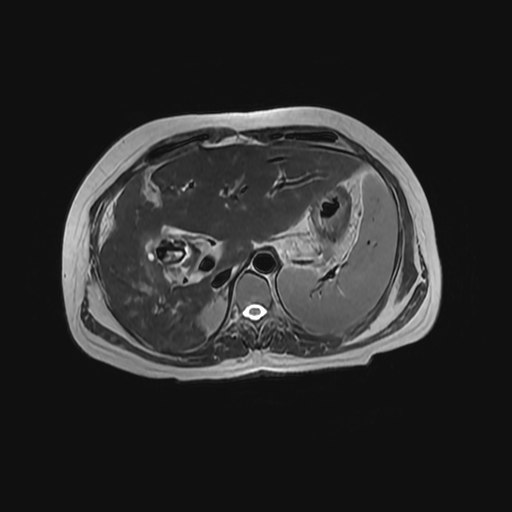

HISTORIA DEL PACIENTE

Paciente de sexo femenino, de 56 años de edad, refiere dolor en cuadrante superior derecho, indica que le realizaron colecistectomía de hace mas o menos 7 años, presenta cuadro de ictericia de 6 meses de evolución. Médico tratante le solicita estudio de Resonancia de vías biliares (Coilangioresonancia)

Se prepara a paciente previo a ingreso a zona 4 del área de resonancia magnética, paciente se presenta con catéter en región anterior del antebrazo, se utiliza bobina de abdomen de 16 canales y se procede a obtener localizadores en los tres planos, para luego adquirir imágenes en diferentes planos, en secuencias espin echo, eco de gradiente, secuencia de difusión. Se utiliza medio de contraste hepatoespecifico con dosis sugerida por fabricante.

HALLAZGOS IMAGENOLOGICOS

Se observa dilatación de las vías intra hepáticas a expensas de sus ramas hepáticas derecha, anterior y posterior, hepática izquierda y hepática común. El hepático común da la apariencia de estar anastomosado a un asa de intestino, lo que sugiere la posibilidad de una cirugía entero biliar.

No se logra observar el colédoco.

1. Dilatación de vías biliares intrahepáticas

2. Anastomosis entero biliar

3. Colangitis aguda